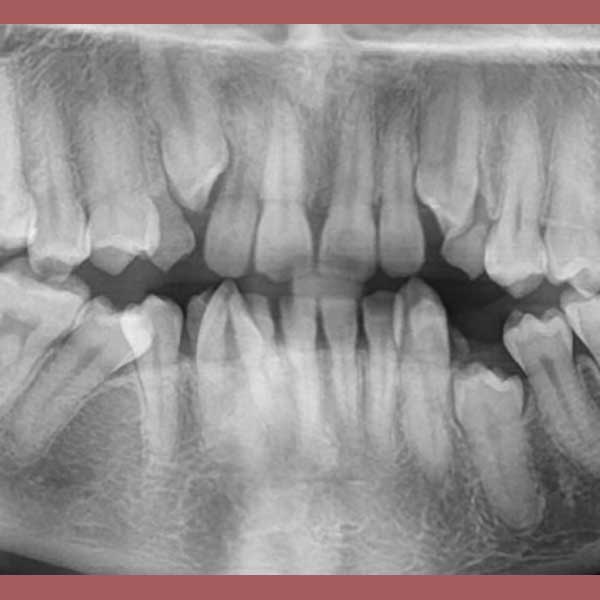

AFTER

By examining the case and taking X-rays, I observed the upper canines in her mouth, and an embedded lower premolar was observed too on the left side, I started the treat the case, but because of the old age of this lady, the upper canines and the left lower premolar did not erupt on their own after we extracted the temporary canines, and she had to pull them out by braces. As for the lower jaw; The canines were pulled back in place and the embedded premolar was orthodontically pulled.

At the end of treatment she asked me to photograph her on her own, because she was happy, and she was able to smile confidently again!